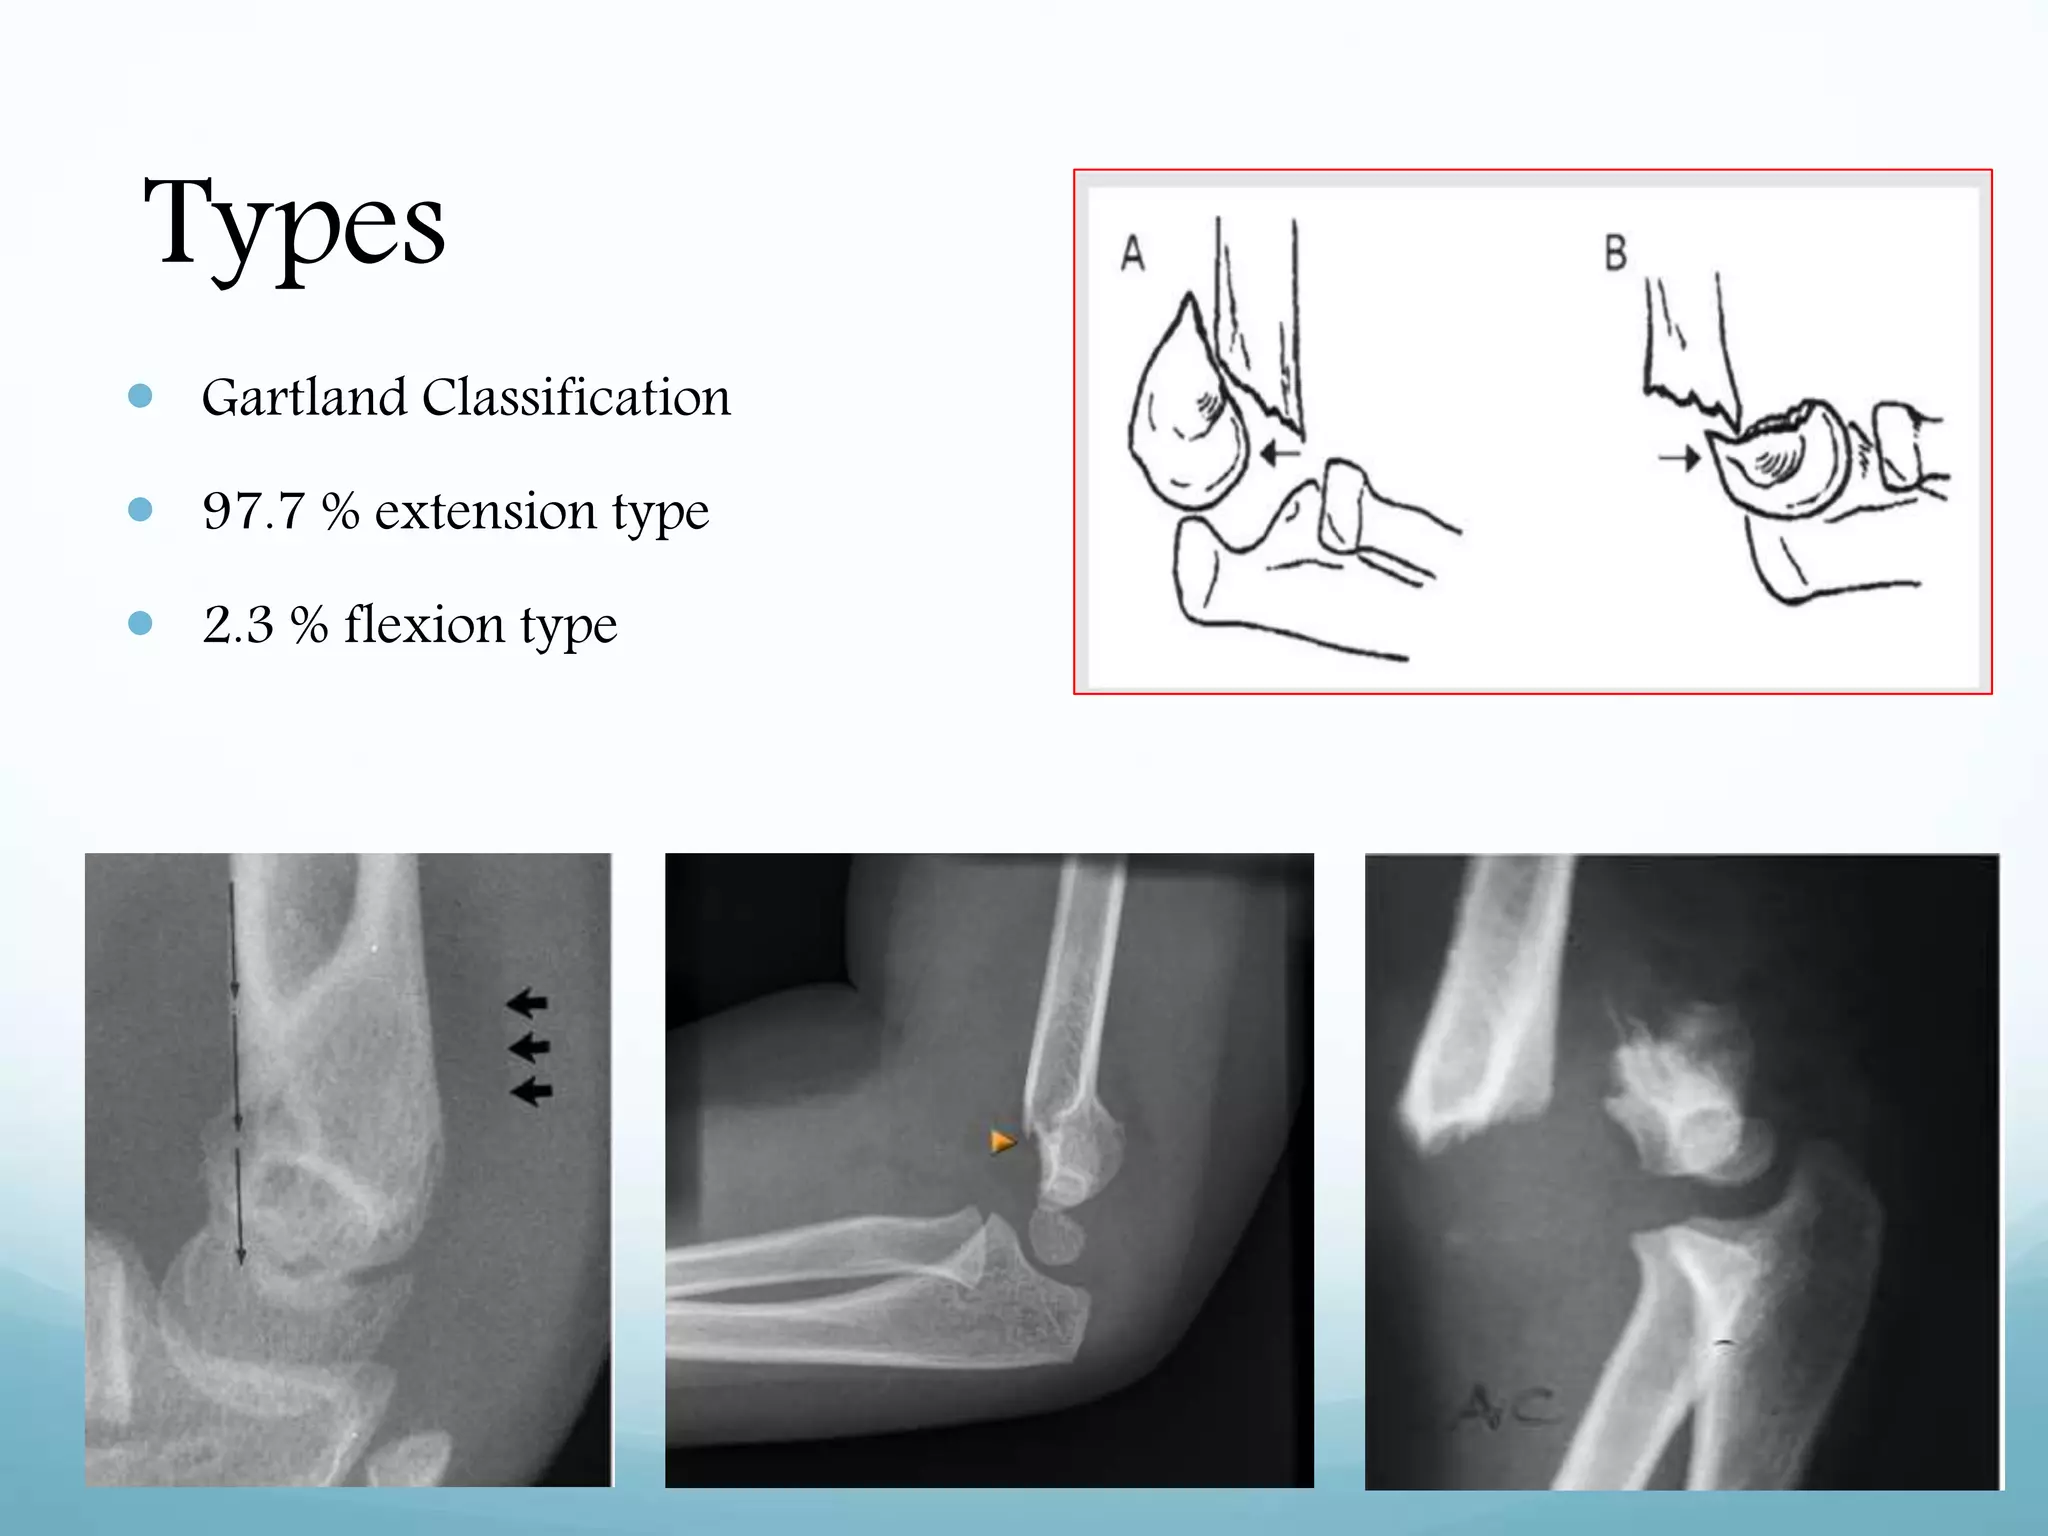

Types

 Gartland Classification

 97.7 % extension type

 2.3 % flexion type

Types  Gartland Classification 97.7 % extension type  2.3 % flexion type